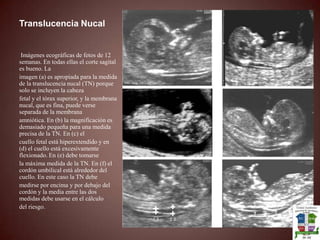

Principios basicos de ecografia obstetrica Vicky

• 1.

PRINCIPIOS BASICOS DEECOGRAFIA OBSTETRICADRA. VICTORIA AMBROSIO